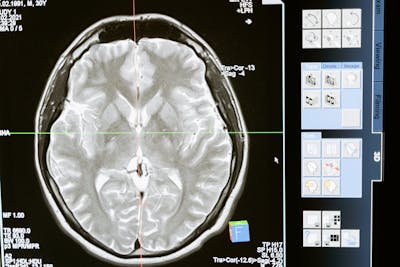

7. Periksa Kesehatan Secara Rutin

Penyakit seperti hipertensi, diabetes, dan kolesterol tinggi dapat memengaruhi aliran darah ke otak. Oleh karena itu, penting untuk rutin memeriksakan kesehatan dan mengelola kondisi medis yang ada.

Saran: Konsultasi rutin ke dokter minimal 2 kali dalam setahun.